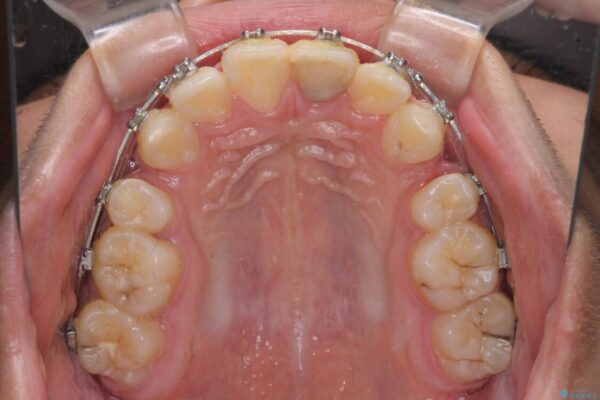

治療途中

• 膨らんだ口元 ワイヤー装置での抜歯矯正 治療途中画像